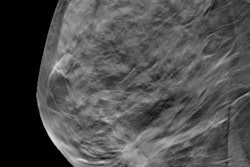

The authors called this tendency a "bias for action," and it underlies the difficulty that the antiscreening lobby is having in getting people to look more critically at screening tests like mammography, specifically by considering the harms of a screening test in addition to its benefits.

While you're in our Women's Imaging Community, check out this story on the accuracy of breast density measurements based on synthesized 2D mammography images (spoiler alert: they compare well to assessments based on regular 2D mammography studies), and be sure to read the latest contribution from Paragon Consulting Partners on how breast imaging facilities may need to change to adapt to the rise of consumerism in women's health.